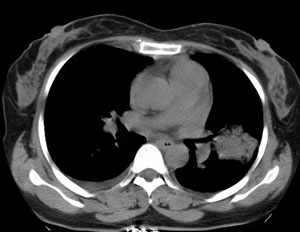

女性,30岁。

病史为胸痛20多天,无畏寒发热,无消瘦,无咳嗽咳痰。总之症状很逍遥。

临床以胸痛待查收住入院。

双肺野可见散在大小不等结节及肿块影,内密度不均匀,边缘部分清,部分欠清,纵隔未见明显肿大淋巴结.右侧胸腔少理积液.结合临床,考虑韦格肉芽肿可能吧,巨淋巴增生,结节病,特殊感染都要考虑.转移瘤临床不象.

本病例特点如下:

1.青年女性,以胸痛20多天就诊,无呼吸道及感染临床症状体征,无原发肿瘤病史;

2.肺ct表现为两肺多发大小不等结节影,大结节位于肺尖部,小结节多位于肺外带胸膜下,大结节内可见支气管充气征,周围可见月晕征(指在结节状或肉芽肿样病灶周围呈环形磨玻璃影),右肺门及腔静脉后可见小淋巴结,右侧胸腔内少量液体。

两肺散在分布大小不等的肿块及结节影,边缘毛糙,有分叶、毛刺,病灶密度不均匀,可见支气管充气相与空泡征。病变大多位于胸膜下,可见胸膜凹陷及胸腔积液。气管腔静脉间可见小结节影。

病人临床仅为胸痛,暂不考虑感染性病变。

考虑多发结节型细支气管肺泡癌。